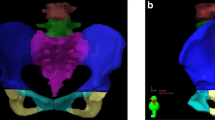

The theorized mechanism for the indirect pathway postulated that irradiation has an effect on local circulation, which therefore inhibits bone remodeling and turnover [5, 28]. Furthermore, radiation-induced devascularization of the bone increases the risk of fracture by denying vital nutrients to bone cells in the blood and causing additional bone loss [26, 29]. Figure 2 shows a schematic depiction of the mechanisms by which RT gradually promotes the growth of PIF in patients with cervical cancer.

According to the findings of several studies, the distribution of pelvic insufficiency-related fractures is shown in Fig. 3. Table 1 provides a review of relevant research on probable fracture locations, including details about each finding.

Ventral view of the pelvic region and the schematic distribution of PIF after RT, according to previous studies. (A) Diagrammatic representation of the female pelvic girdle. (B) PIF was observed at the sacral-iliac joints (32 sites, 72%), pubis (9 sites, 20%), acetabula (2 sites, 4%), and lumbar spine (1 site, 2%), according to Tokumaru et al. (C) The sacroiliac joint, which was shown in 15/22 fractures (68%), and pubic bone, which was seen in 4/22 (18.5%), were the most common fracture sites, according to Shih et al. (D) Sixty-one patients (61%) who experienced multiple pelvic insufficiency fractures, of whom 40 (40%) had bilateral symmetric lesions of the sacral alae and eighty-five patients (85%) had sacral involvement, Kwon et al. (E) The distribution of PIF involvement was as follows, according to Abe et al.: sacroiliac joint in 61% (sacral ala in 53% and a medial region of ilium in 8%), upper sacrum (S1 -S2) in 28%, lower sacrum (S3-S5) in 4%, pubis in 4%, and ischium in 3%. The non-irradiated iliac wing was never affected. 23 (85%) of the 27 patients had more than one area of increased activity